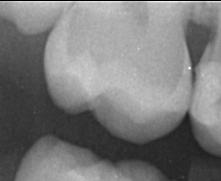

Zur professionellen Vorsorge gehört unserer Ansicht nach auch eine umfangreiche Diagnostik. Diese versuchen wir mit technischen Hilfsmitteln auf den neuesten Stand der Technik zu halten. So haben wir nun auch mit der DiagnoCam ein Hilfsmittel zur strahlungsfreien Kariesdiagnostik..

Mit der neuen DiagnoCam kann mittels Licht zwischen die Zähne geschaut werden.

Hier ein klinisches Beispiel aus der Praxis: Man kann die Kontaktpunktkaries gut erkennen , die aber röntgenologisch nicht eindeutig festgestellt werden konnte. Die Diagnocam bietet eine  gute strahlungsfreie Diagnosealternative.